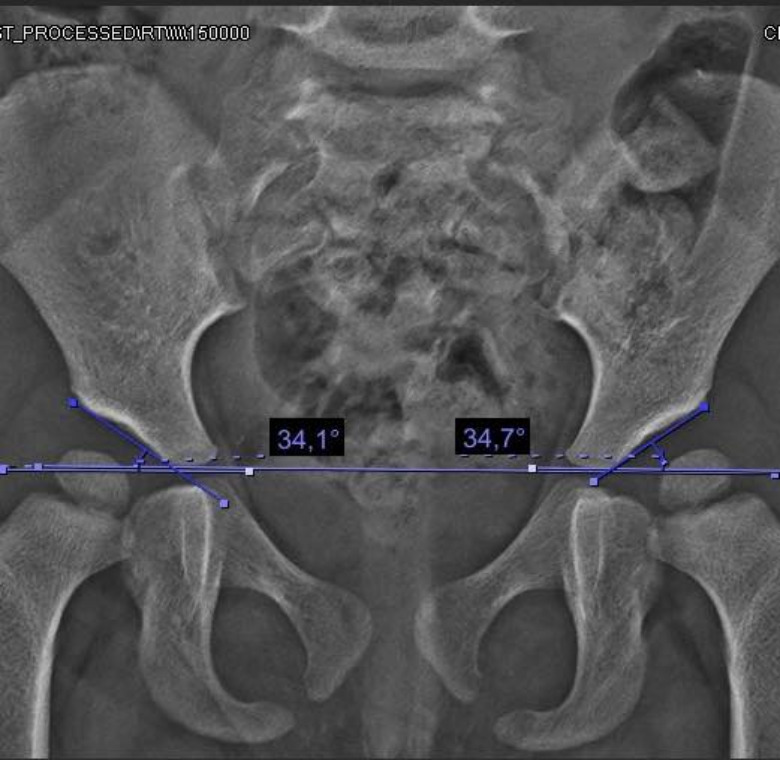

Displasia de cadera